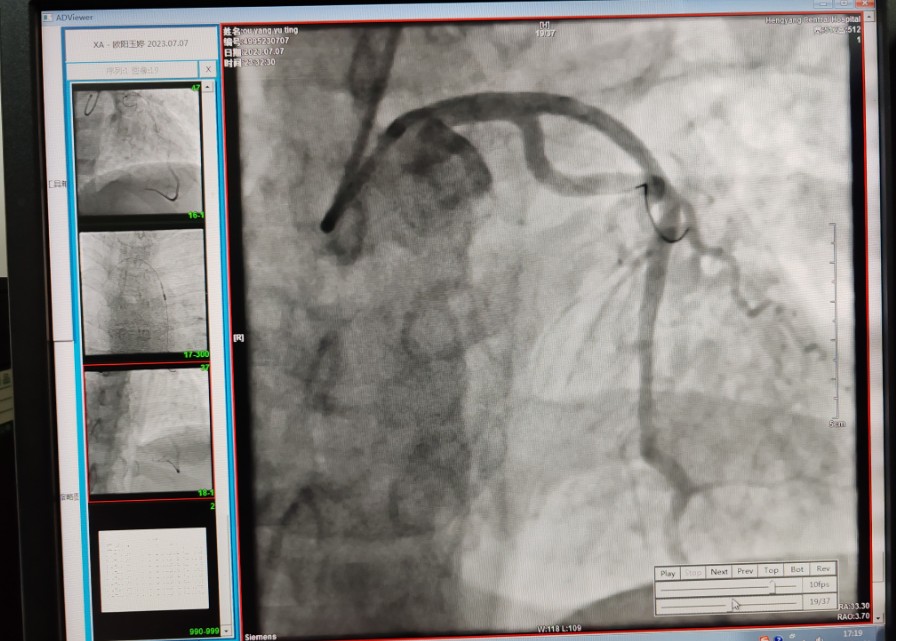

22:29分患者經(jīng)院內(nèi)綠色通道送達(dá)導(dǎo)管室,手術(shù)由雷剛副主任醫(yī)師主刀,楊繼賀副主任醫(yī)師為第一助手,介入技師及護(hù)士密切配合,聞?dòng)嵍鴣淼内w慶禧主任醫(yī)師坐鎮(zhèn)協(xié)調(diào)指揮。22:37分手術(shù)開始,冠脈造影顯示心臟上最重要的一條冠狀動(dòng)脈-前降支開口齊頭閉塞,血管粗大且血栓高負(fù)荷,非??简?yàn)介入術(shù)者的手術(shù)能力,一旦發(fā)生冠脈無復(fù)流或操作不慎血栓帶入回旋支導(dǎo)致循環(huán)崩潰,病人幾乎無生還希望;此時(shí),患者手術(shù)臺(tái)上仍持續(xù)胸痛,且血氧飽和度在高流量吸氧狀態(tài)下不到80%,雷剛副主任醫(yī)師一方面指揮鎮(zhèn)靜鎮(zhèn)痛及抗心衰治療,一方面緊急啟用IABP(主動(dòng)脈球囊反搏),然后精細(xì)操控細(xì)如發(fā)絲的介入導(dǎo)絲迅速通過病變,并予冠脈球囊擴(kuò)張、冠脈內(nèi)溶栓、抗痙攣藥物使用、植入冠脈支架,最終成功開通“罪犯”血管,且無手術(shù)并發(fā)癥發(fā)生,整個(gè)過程張弛有度、快慢結(jié)合、一氣呵成。患者術(shù)后胸痛明顯好轉(zhuǎn),血氧飽和度上升至96%,術(shù)后1天轉(zhuǎn)出監(jiān)護(hù)病房,第3天拔出IABP,目前已康復(fù)出院。